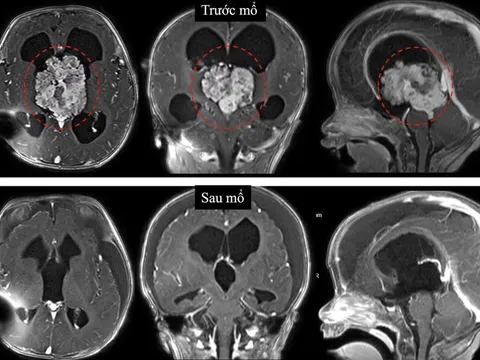

Tối ngày 14/3, BV Đa khoa Vũng Tàu tiếp nhận bệnh nhân V.Q.C (58 tuổi) trong tình trạng hôn mê sâu sau tai nạn giao thông. Với điểm Glasgow chỉ còn 5 điểm, kèm khối máu tụ ngoài màng cứng vùng trán và nứt sọ diện rộng, bệnh nhân đối mặt với nguy cơ tử vong cận kề.

Ngay khi có mặt lúc 0 giờ 15 phút ngày 15/3, ca phẫu thuật giải áp, lấy khối máu tụ được tiến hành khẩn trương. Sự phối hợp hiệu quả giữa các chuyên gia TP.HCM và đội ngũ tại chỗ đã tận dụng tối đa "thời gian vàng", giúp bệnh nhân vượt qua cơn nguy kịch, giảm thiểu tối đa các di chứng thần kinh hậu phẫu.